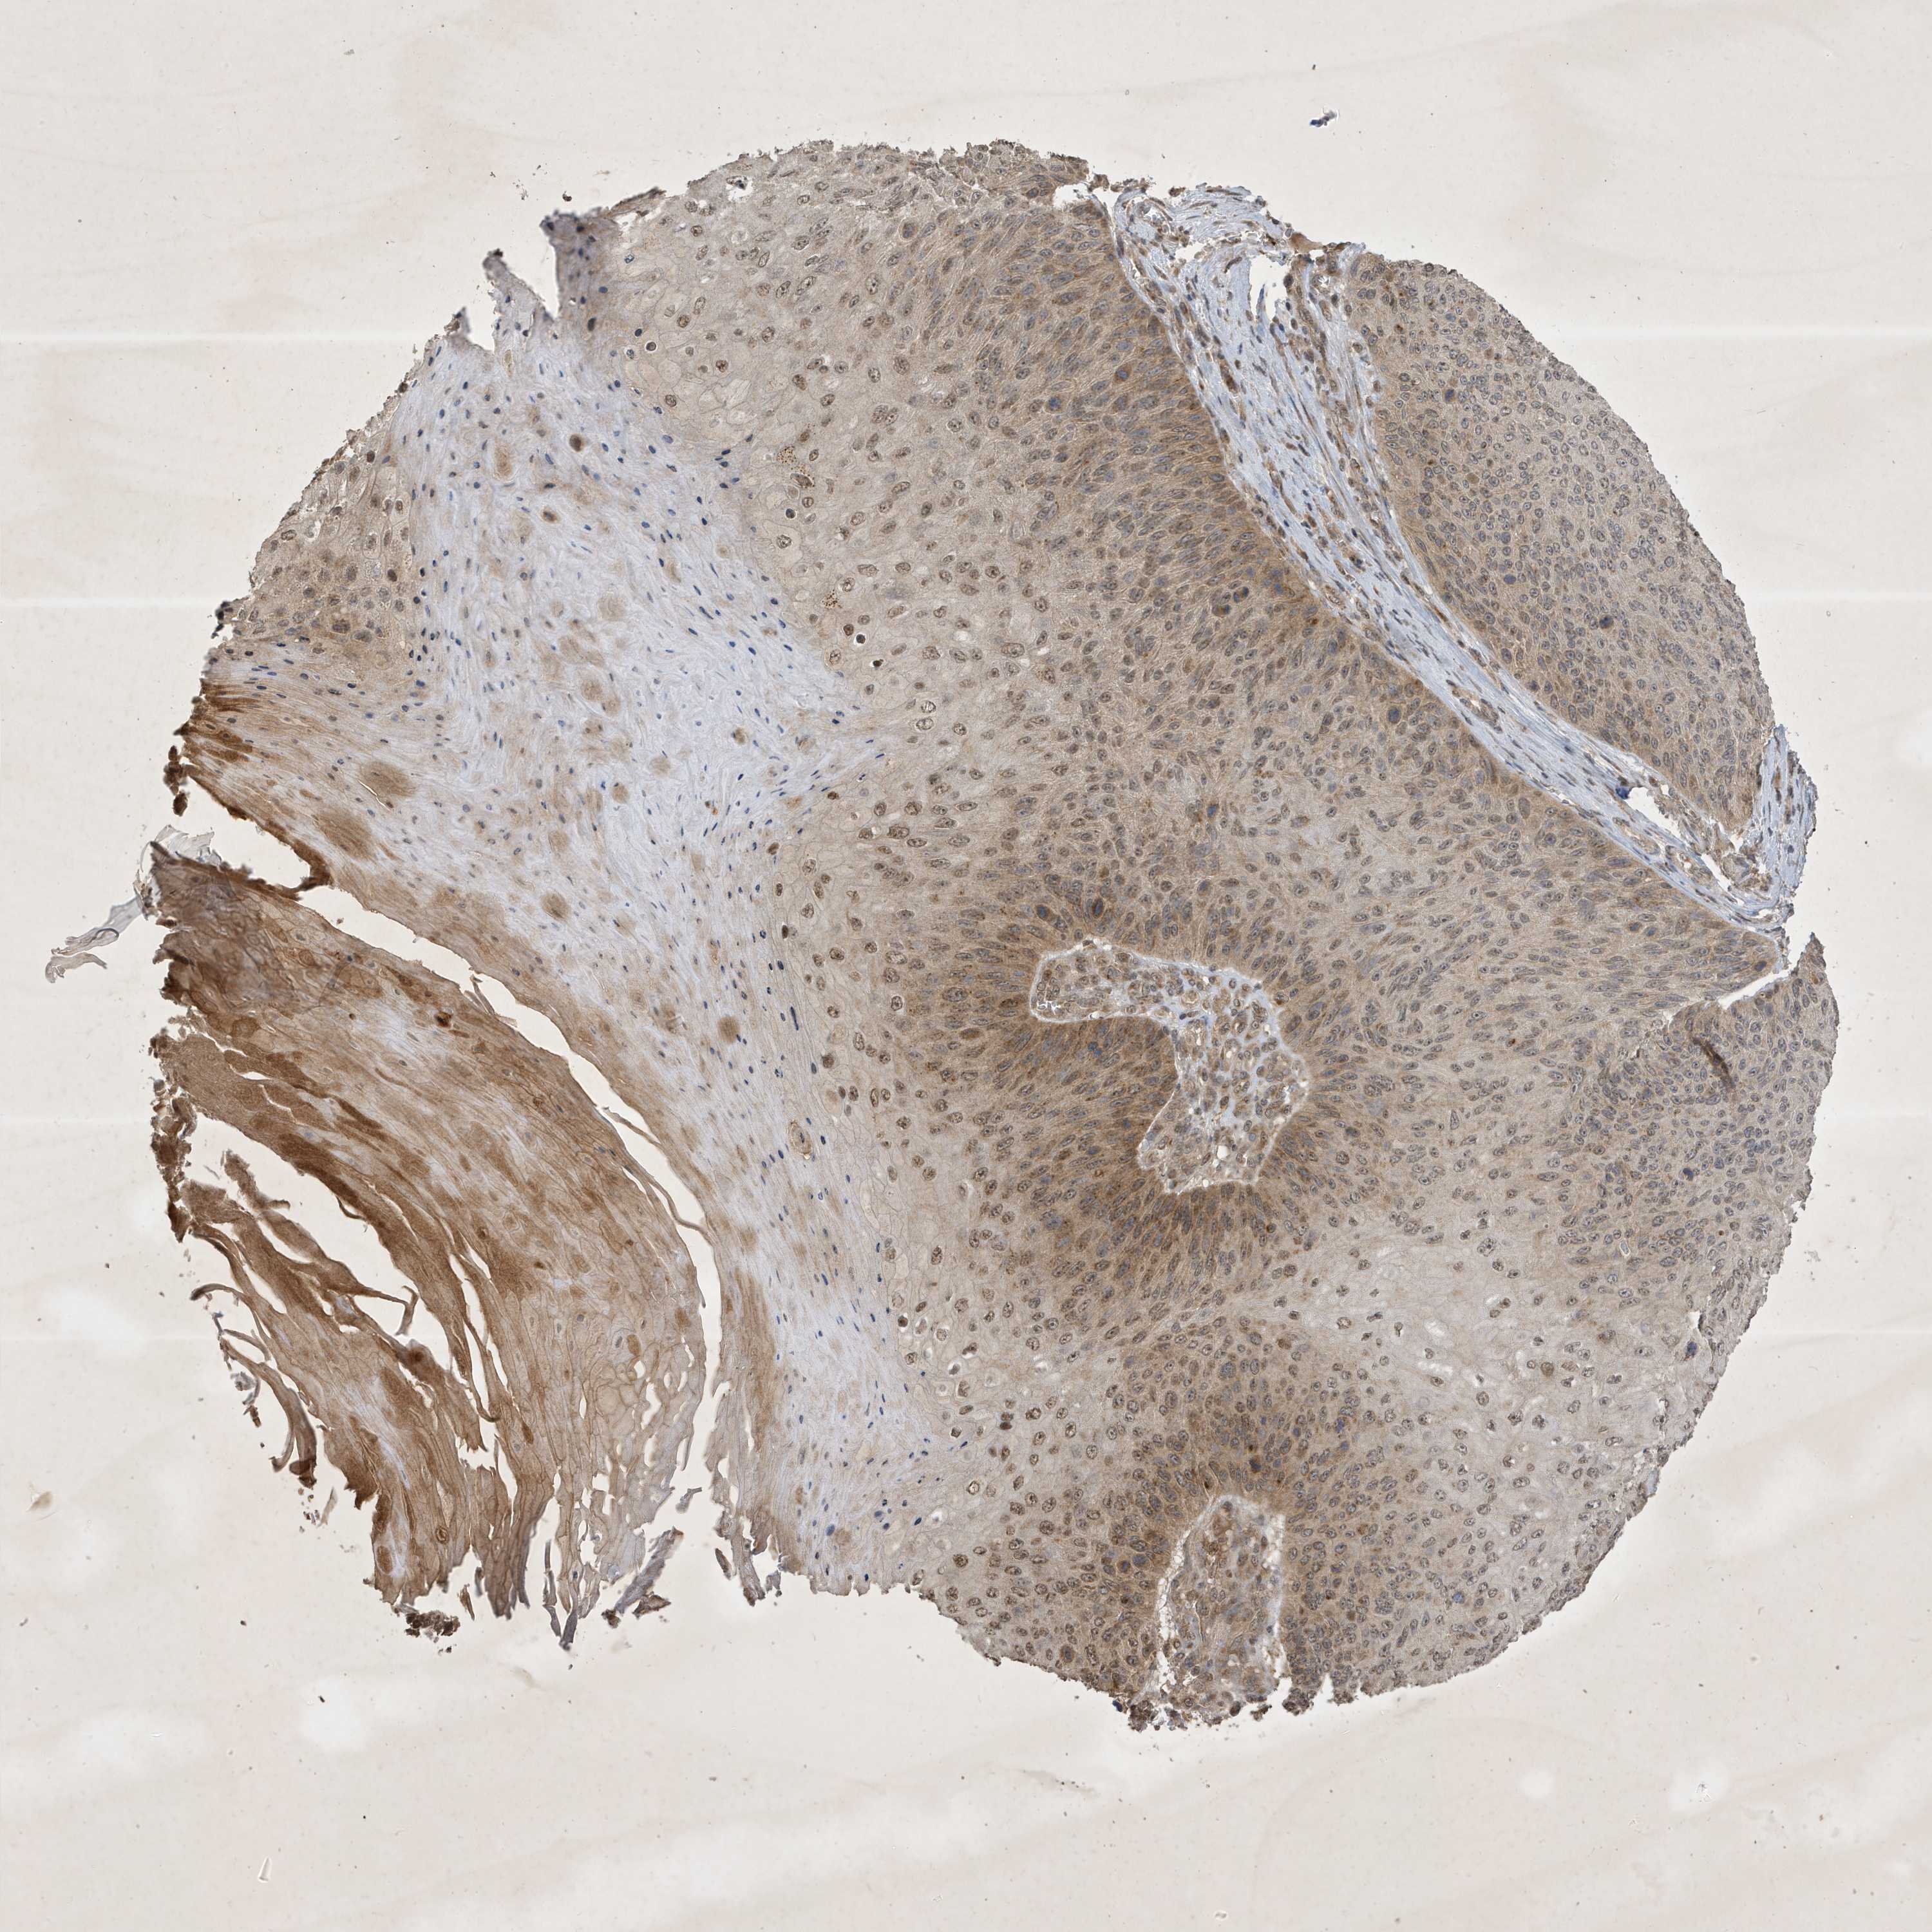

SKIN CANCER - Protein expressioni

A mouse-over function shows sample information and annotation data. Click on an image to view it in a full screen mode. Samples can be filtered based on level of antibody staining by selecting one or several of the following categories: high, medium, low and not detected. The assay and annotation is described here.

Antibody stainingi

Antibody staining in the annotated cell types in the current human tissue is reported as not detected, low, medium, or high, based on conventional immunohistochemistry profiling in selected tissues. This score is based on the combination of the staining intensity and fraction of stained cells.

Each image is clickable and will lead to virtual microscopy that enables deeper exploration of all samples and also displays staining intensity scores, fraction scores and subcellular localization as well as patient and tissue information for each sample.

Antibody HPA035303

Staining

High

Medium

Low

Not detected

Intensity

Strong

Moderate

Weak

Negative

Quantity

>75%

75%-25%

<25%

None

Location

Nuclear

Cytoplasmic/membranous

Cytoplasmic/membranous,nuclear

Basal cell carcinoma